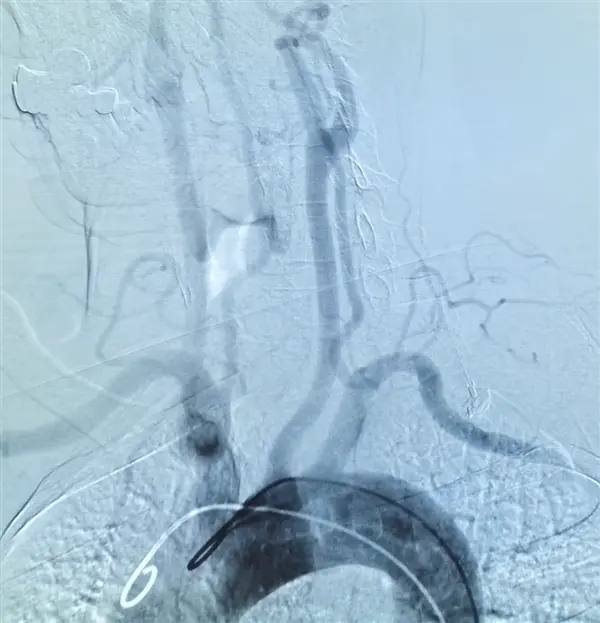

“幸运”的是,家人曾经得过脑卒中,所以立刻将其送医,及时通过动脉溶栓手术治疗,半小时后就完全恢复。